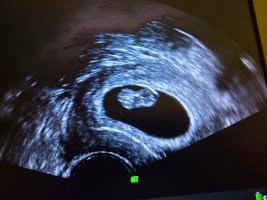

Pga risikosvangerskap skal jeg følges tett opp, og fikk derfor uventet en ultralyd i dag også for å bekrefte liv før mølla settes i gang. 8+1 (mensdato 8+5) og hun klarte faktisk å ta utvendig ultralyd (new achievement unlocked). Lille ble nå målt til ca 8+2

Og på de 8 dagene har lille vokst nesten 1 cm!

Ca 1,76-1,78 cm